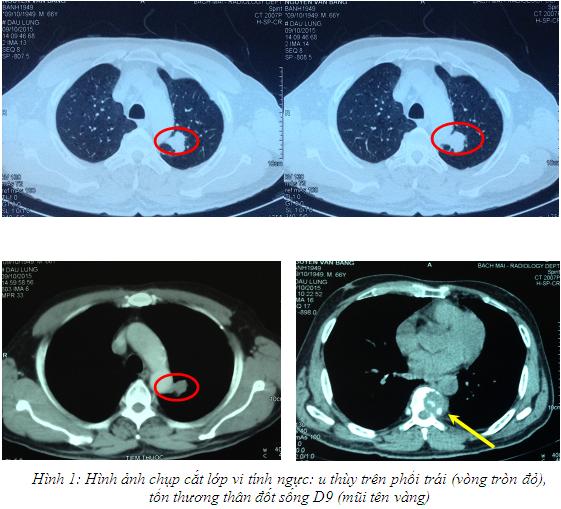

* Chụp cắt lớp vi tính lồng ngực:

U thùy trên phổi trái kích thước 20x23mm, tổn thương phá hủy

thân đốt sống D9.

– Do tổn thương u thùy trên phổi trái nằm cạnh

cung động mạch chủ ngực nên có thể có nhiều nguy cơ tai biến nếu sinh thiết u

phổi trái. Vì thế bệnh nhân đã được tiến hành sinh thiết tổn thương thân đốt

sống D9 dưới hướng dẫn chụp cắt lớp vi tính.